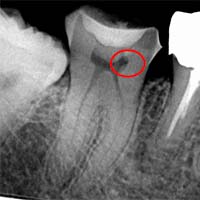

大きな根尖病変(根の先の膿・嚢胞)

根の先端に大きな“黒い影(透過像)”がある場合、それは細菌感染によって骨が溶けた状態を示します。

診断ではこの病変を立体的に観察できます。

病変の大きさ=歯が残せない、ではありません。MTAの封鎖力の高さにより、根の先端の炎症が治まり、骨が再生していく症例は多くあります。

Torabinejad(1995)MTAの高い封鎖性・生体親和性: